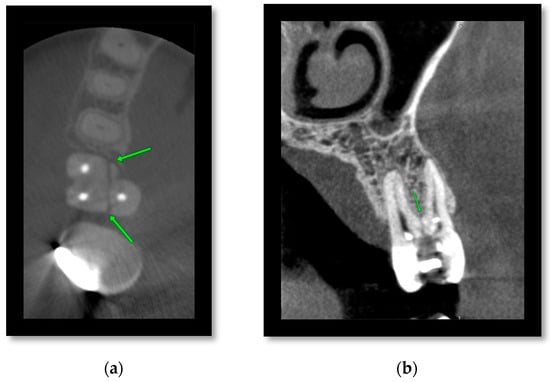

3.1. Cone Beam CT for Assessment of Dentoalveolar Fractures